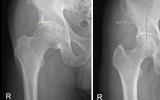

[제주건강보고서] [제주, 제주인의 건강보고서 Ⅷ 건강다이어리] (143)대퇴비구 충돌증후군(FAI)

뼈끼리 부딪쳐 관절 손상 유발신체·영상 등 정확한 진단 필수스트레칭·저강도 운동 등 도움 [한라일보] 현대인의 반복되는 좌식 생활과 운동 패턴의 변화로 인해 고관절 문제를 겪는 사례가 증가…